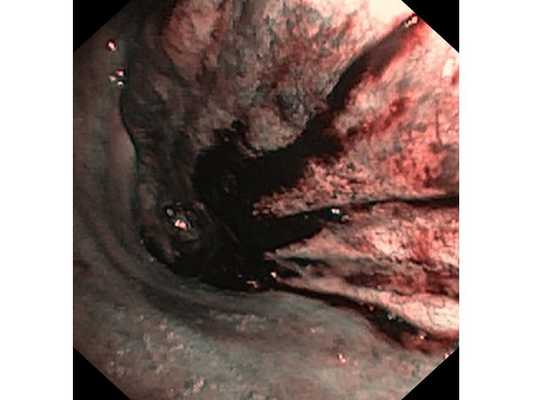

Первым этапом пациенту была проведена фибробронхоскопия, по данным которой выявлено, что устье нижнедолевого бронха слева сужено за счёт подслизистого и перибронхиального распространения опухоли.

Выполнена многократная биопсия из устья нижнедолевого бронха слева. По данным гистологического исследования материала эндоскопической биопсии верифицирован диагноз немелкоклеточного рака лёгкого.

Чтобы провести первичное стадирование опухоли, пациенту проведена позитронно-эмиссионная томография в сочетании с компьютерной томографией (ПЭТ-КТ). По данным исследования, выявлена метаболически активная опухоль в корне левого лёгкого с бугристыми контурами размерами 41 х 43 мм. В толще опухоли проходят нижнедолевой бронх и бронх 6-го сегмента левого лёгкого, просветы бронхов значительно сужены. Нижняя доля левого лёгкого уменьшена в размерах за счёт того, что сегменты 6, 9 и 10 субтотально (частично) инфильтрированы и безвоздушны. Лимфатические узлы корня лёгкого и средостения не увеличены в размерах и не накапливают радиофармпрепарат (РФП), который был введён пациенту перед обследованием внутривенно. Других очаговых образований и очагов гиперметаболизма в организме не обнаружено.

При этом отмечено, что опухоль распространяется в средостение по нижней стенке левого главного бронха и широко прилежит к нижнегрудному отделу аорты (по заключению специалиста ПЭТ-КТ — имеется инвазия опухоли в ткани средостения и возможное врастание в стенку аорты). При самостоятельном пересмотре изображений отмечено, что "опухолевая" ткань, которая распространяется по нижней стенке левого главного бронха в средостение, не накапливает РФП (т. е. не является злокачественной), а стенка аорты в области "инвазии" опухоли имеет ровный чёткий контур и адвентициальную границу, что также свидетельствует об отсутствии онкологического процесса в этой области.